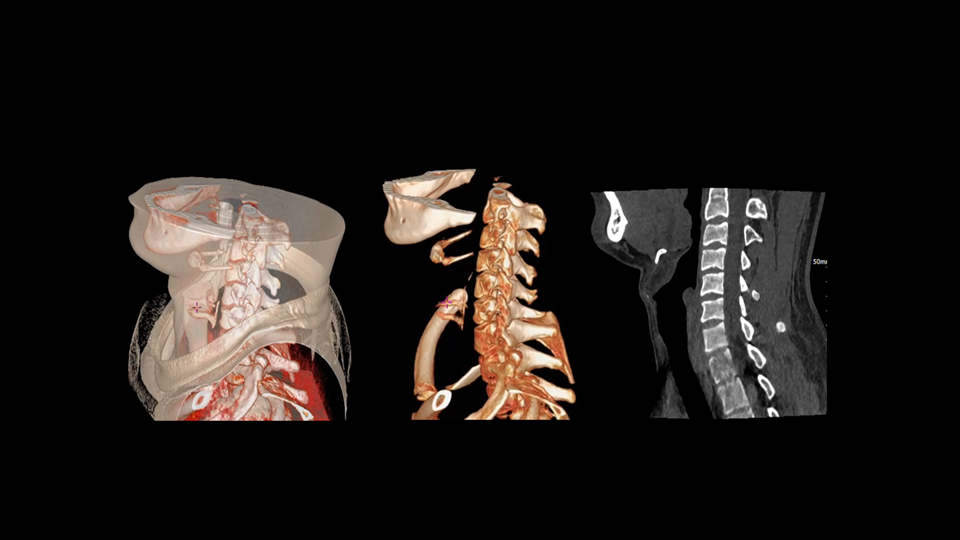

全身各部位动态CT成像

去金属伪影,影像更纯净

uCT SiriuX® 提供系统化金属伪影抑制解决方案。能谱扫描结合 PureBeam 纯光滤能技术,从源头有效减少硬化伪影;DeepMAC深度学习金属伪影校正算法针对射线饥饿、散射等多种成因进行优化重建,从物理与算法双层面显著提升金属植入区域的图像质量与可诊断性。

高能级虚拟单能成像

双宽能谱成像提供高能级虚拟单能图像,结合硬化伪影校正技术,有效提升金属与组织对比度,源头抑制金属物质类硬化伪影。

PureBeam纯光滤能技术

DeepMAC深度学习金属伪影校正算法

基于深度学习网络模型,应对髋关节置换体、脊柱内固定器、四肢骨科植入物、牙科修复体以及血管介入弹簧圈等各类金属植入物伪影,还原清晰解剖结构。